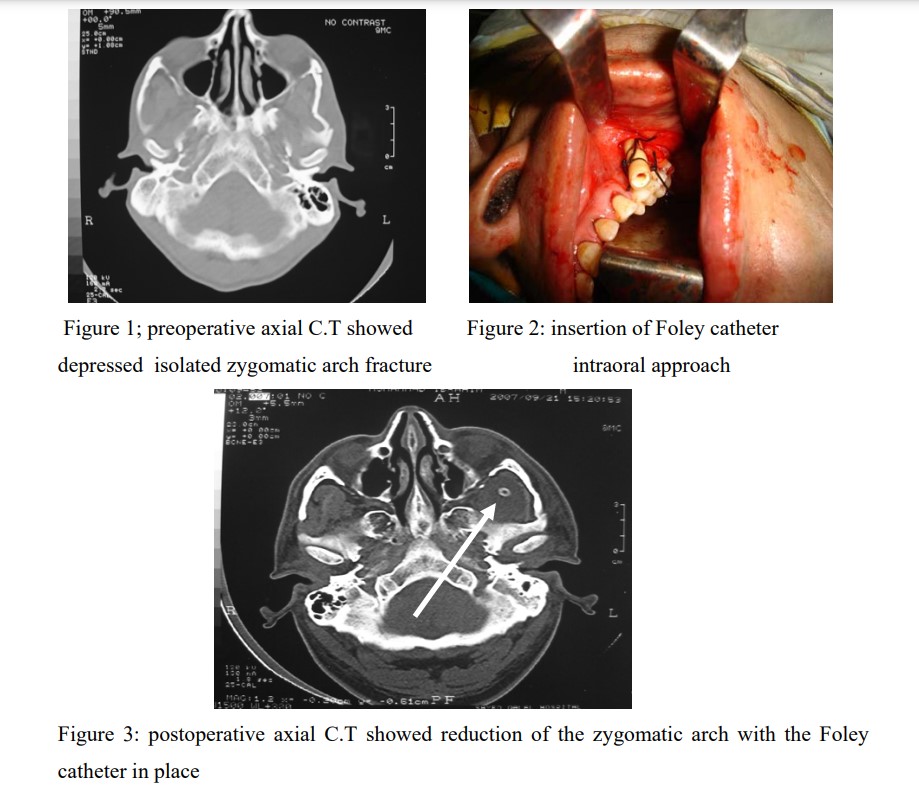

Five patients with isolated depressed Zygomatic arch fracture were included in this study. The type and the extent of the fracture were diagnosed by computed tomographic scan in axial plane (figure 1). Intraoral approach (keen approach) was used for reduction of the Zygomatic arch using the Rowe zygoma elevator and insertion of the Foley Catheter under the Zygomatic arch (figure 2). Normal saline was used to inflate the Foley Catheter balloon for stabilization of the Zygomatic arch. In one patient, the displacement of the arch was mild and in such case, the Foley catheter was used for reduction and stabilization of the displaced arch. Immediate postoperative axial C.T was used for evaluation of the reduction of the Zygomatic arch and for evaluation of the position of the Foley catheter (figure 3). The Foley catheter was removed after three weeks.

Stabilization of the Zygomatic arch fracture by the Foley Catheter was done and the fracture alignment was established perfectly. One patients’ exhibits infection at the intraoral approach treated with antibiotic for five days and two patients reveal difficulty in mouth opening with the catheter balloon in place and this compliant disappeared after removal of the catheter. One year follow-up showed good functional and cosmetic results. None of the patients showed evidence of disturbance of the facial nerve function or persistent trismus.